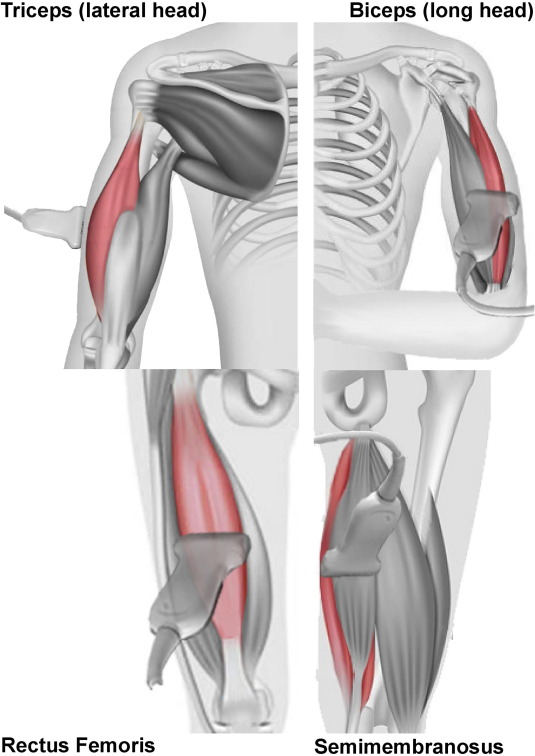

This is a 60-year-old woman with a history of ischemic stroke 5 years ago, previously presenting with aphasia and right-sided weakness, with complete recovery. She now presents with recurrent aphasia and right-sided weakness. In the ED, she was found to have a urinary tract infection with sepsis. MRI brain DWI showed no new diffusion restriction. After 2 days of antibiotics, her neurological deficits completely resolved. Question: What do you see on the MRI? How do you explain her recurrent aphasia and right-sided deficits despite no new imaging changes? #Neuroradiology #Neurology #Stroke #UTI #FOAMed